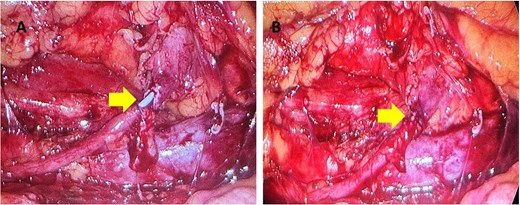

One month later a laparoscopic repair of the RU was completed. Under general anaesthetic the patient was placed right side up. A pneumoperitoneum was created with the Kii Fios first entry system and a 5 mm camera, two additional ports were used (5 mm and 12 mm). The ascending colon was mobilized medially and the IVC identified. Careful dissection allowed identification of the RU (Fig. 4). The ureter was fully mobilized behind the IVC, then divided and spatulated. Two 4.0 vicryl stay sutures were used to anastomose the apex of the spatulated ureter to proximal ureter. The posterior uretero-ureteral anastomosis was performed with interrupted 4.0 vicryl sutures. A 6 French (Fr), 24 cm JJ stent was placed into the ureter and the anterior anastomosis was performed again with interrupted 4.0 vicryl sutures (Fig. 5A and B). A 16Fr non-suction drain and a 16Fr urinary catheter were placed.

Mobilization of the ascending colon medially has exposed the IVC (red arrow) and the ureter (yellow arrows). Note how the ureter passes behind the IVC. The gonadal vein needed to be removed. Note the hem-O-Lok clip on the vein coming off the IVC.

(A, B) The yellow arrow is pointing to incomplete uretero-ureteral anastomosis. The blue JJ stent is visible. In Fig. 5(B) the anastomosis is complete.

The total operative time was 138 min with a blood loss of 50 mL.